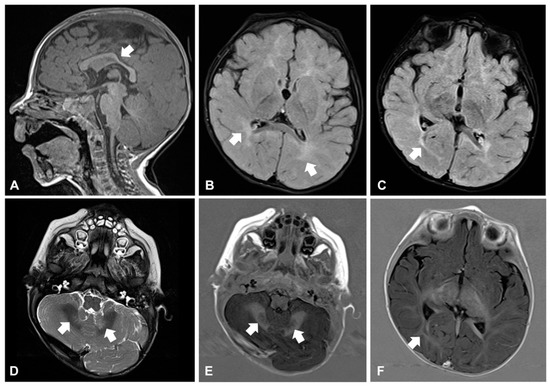

Around the age of 10 months, he developed daily clusters of sudden and repeated flexions of arms and trunk, which were consistent with epileptic spasms. Electroencephalogram (EEG) showed hypsarrhythmia: West syndrome was diagnosed and therapy with vigabatrin started. Brain magnetic resonance imaging (MRI) revealed reduction and hyperintensity of the deep and periventricular white matter in the T2-weighted and FLAIR images, modestly hypodysplastic corpus callosum, and mild abnormal signal of the cerebellar dentate nuclei (Figure 2A–F). Electroretinogram was normal, while visual evoked potentials (VEP) revealed markedly increased latency and poor morphological definition, indicative of alteration of the retro-retinal visual pathways. The child also manifested feeding difficulties and recurrent respiratory infections with delayed growth. A gastroesophageal scintigraphy showed markedly delayed gastric emptying and severe gastroesophageal reflux (GER) associated with pulmonary aspiration, confirmed by salivogram. Percutaneous endoscopic jejunostomy was performed to ensure sufficient nutrient intake.

Figure 2. Brain magnetic resonance imaging in patient 1 at age 10 months. Corpus callosum is thin and mildly dysplastic at the level of isthmus (arrow in (A), sagittal view, T1-weighted image). The deep and periventricular white matter appears hyperintense compared to the grey matter (arrows in (B), axial view, FLAIR image), a similar abnormal high signal also involves the optic radiations (arrow in (C), axial view, FLAIR image). Finally, mild hyperintensity of the cerebellar dentate nuclei is visible (arrows in (D), axial view, T2 weighted image). T1-IR images confirm the involvement of dentate nuclei (arrows in (E), axial view) and optic radiations (arrow in (F), axial view).

We describe the first two Italian patients with neuro-ichthyotic syndrome due to ELOVL4 biallelic mutations. To date, only two sporadic cases from Saudi Arabia and India, respectively, and a Pakistani family have been reported [5,6]. Both our patients were born as a mild collodion baby similar to a single previous case [5]. Ichthyosis was characterized by slight hyperkeratosis, fine whitish scaling, and flexural erythema, consistent with previous reports [5,6]. In addition, one patient developed palmoplantar keratoderma, a feature not yet described. The mild skin phenotype was associated with major neurological manifestations comprising early-onset drug-resistant epilepsy, intellectual disability and spastic-dystonic tetraparesis, in line with the severe neurological impairment observed in the first two cases described [5]. However, only one of the three affected Pakistani siblings had typical neurological manifestations, indicating that intra-familiar phenotypic variability can occur [6]. Neuro-imaging is available only for one previous patient, who presented a severely delayed myelination and brain atrophy at 6 months of age [5]. Our findings seem to support the presence of white matter involvement. However, both our patients had a single brain MRI performed in the first year of age, thus limiting accurate evaluation of the myelination process. Nevertheless, the involvement of optic radiations and cerebellar dentate nuclei seen in patient 1 at 10 months is indicative of altered myelination since these structures are normally myelinated around 1 year of age. Ophthalmological examination of our patients confirmed lack of macular changes specific for Stargardt disease type 3 [5,6]. On the other hand, in both our patients VEP indicated alteration of the retro-retinal visual pathways. Interestingly, IKSHD syndrome due to ELOVL1 dominant mutations presents progressive loss of visual acuity and peripheral vision secondary to optic atrophy [12]. Furthermore, marked growth delay was present in our patients as well as in the first two described cases [5]. Our patient 1 also showed mild facial dysmorphism, a feature not previously reported. Finally, our cases presented severely delayed gastric emptying, as frequently observed in severe encephalopathies.